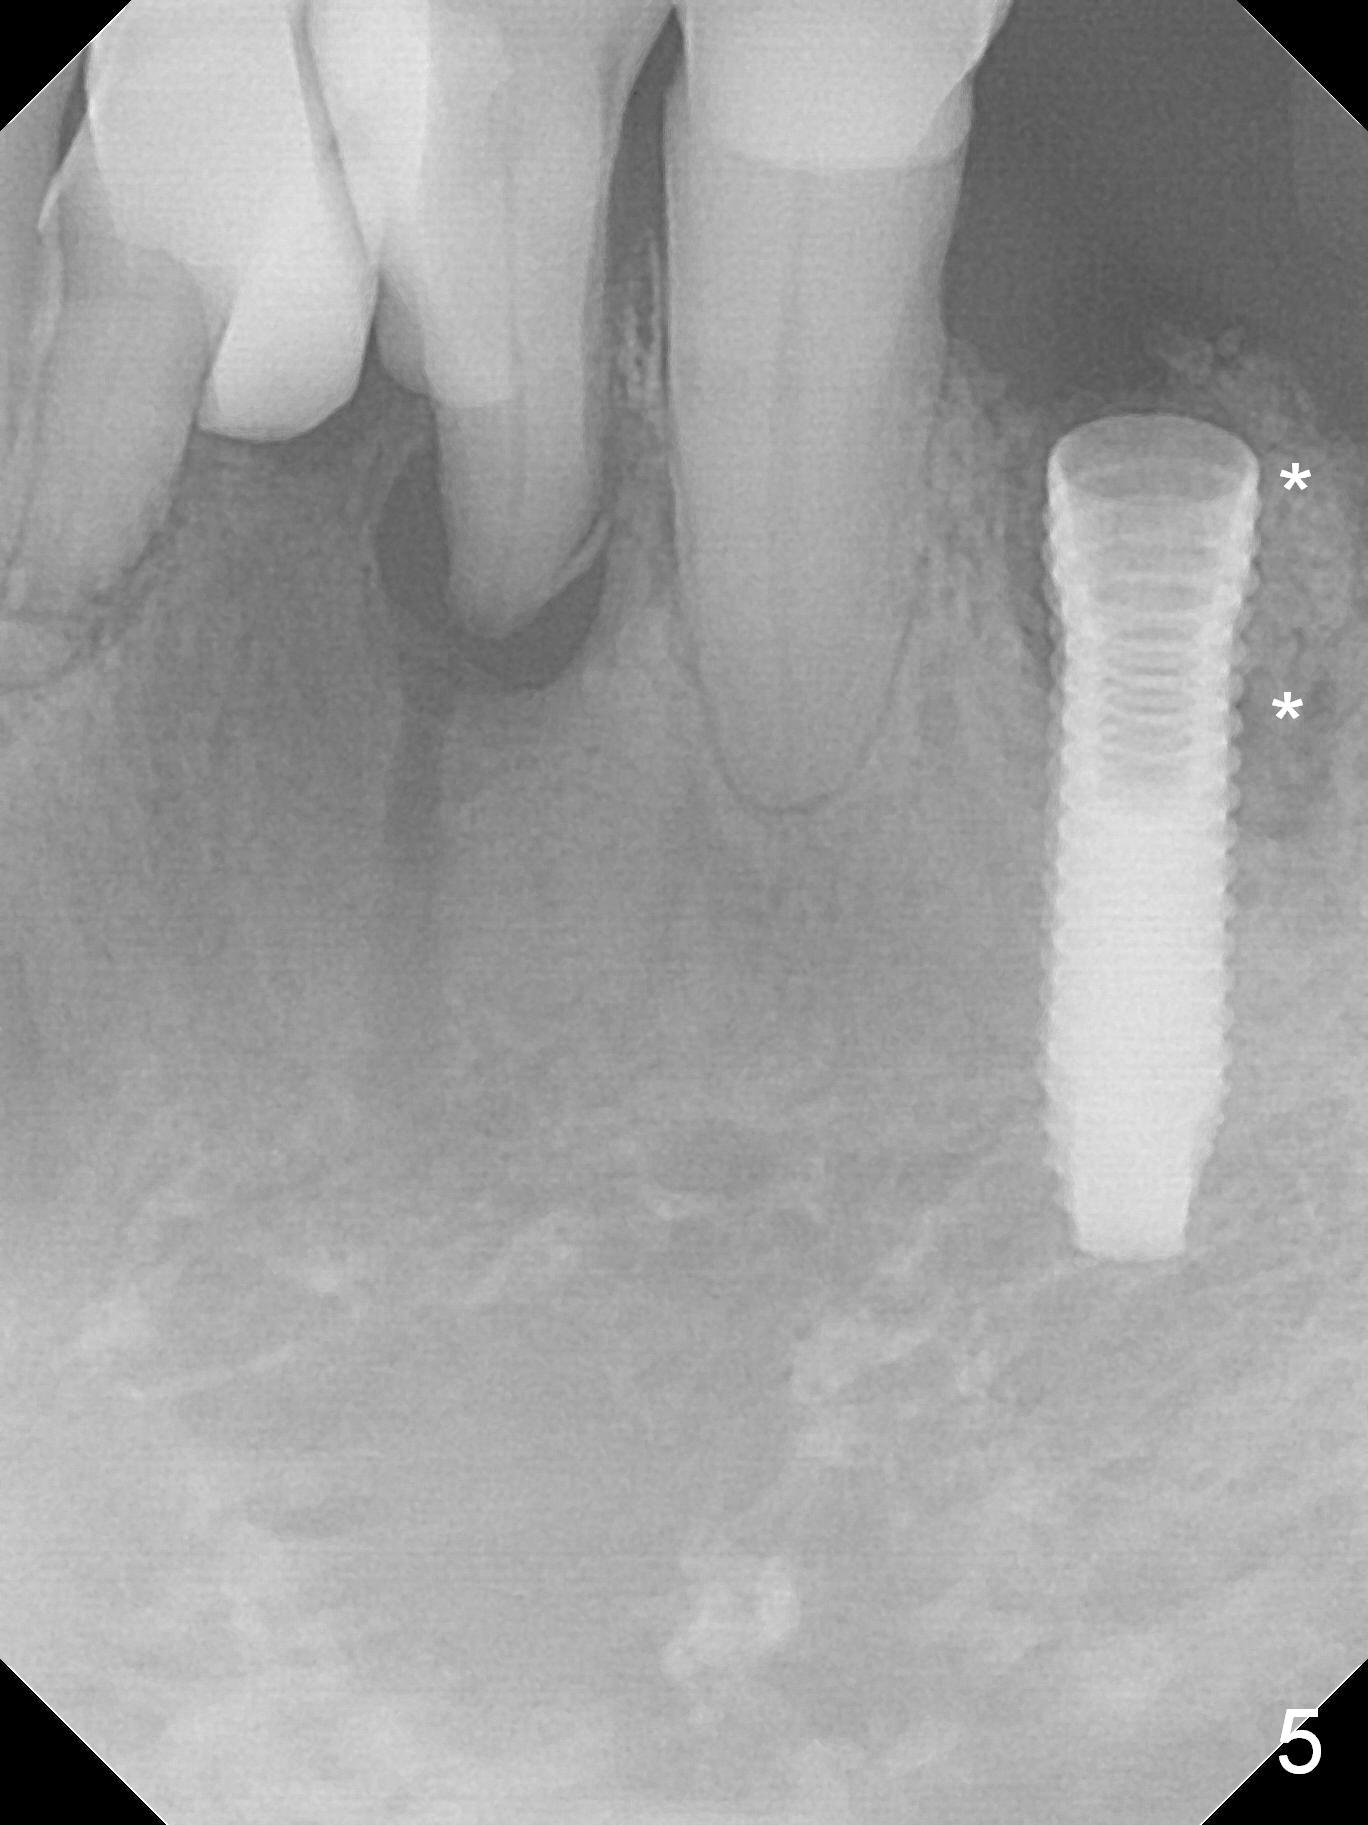

A 72-year-old man presents to clinic for implants because of pain associated with wearing the lower partial. The teeth #21, 24, 25 and 31 seem to be non-salvageable and are going to be replaced by implants so that the lower RPD can be reused (Fig.1). The edentulous ridge is atrophic (Fig.9 *). The upper complete denture appears to be functional. Since the tooth #21 is symptomatic (Fig.2) and the patient has chronic TMJ dislocation, the affected tooth is extracted first (Without antibiotic socket treatment) for immediate implant (Fig.3 (1.5 mm drill (placed more lingually)). The lower RPD is used as a surgical guide (Fig.4 (3 mm drill in place)). When a 3.8x16 mm implant is placed with bone graft (Fig.5 *), the underlying neurovascular bundle is undetected. A small field of panoramic X-ray is retaken; it seems that there is enough clearance from the Mental Foramen (Fig.2,6,7 (red dashed line)) and the Incisive Canal (pink dashed line). The implant is then placed 2 mm more apically (Fig.7) to reduce the chance of periimplantitis since the buccal plate is lost. A 5.5x5(5) mm abutment is placed (Fig.5) with more graft. The access of the abutment is left open so that a part of periodontal dressing is inserted for additional retention (Fig.8,9). The RPD is placed back for adaptation of the dressing. The patient is advised not to wear the RPD postop to reduce micromovement.